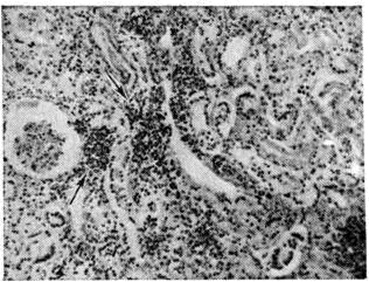

Поражения почек при Лептоспироз наиболее часто выявляют в поздние сроки болезни. В это время лептоспиры начинают выводиться с мочой. На вскрытии почки значительно увеличены в размерах, дряблые, на разрезе желтушные. Могут встретиться кровоизлияния в мозговое вещество и околопочечную клетчатку. Гистологически преобладает картина нефроза, вплоть до некроза эпителия извитых канальцев. Клубочки поражаются меньше, чем канальцы. В просвете канальцев могут быть обнаружены лептоспиры. Наряду с явлениями нефроза возможны мелкоочаговые круглоклеточные инфильтраты в интерстиции почки (рисунок 3).

Информация об Ordo Deus Перейти в оглавление сайта

Рис. 3.

Микропрепарат ткани почки при лептоспирозе: мелкоочаговыс круглоклеточные инфильтраты в интерстиции почки (указаны стрелками); × 200.